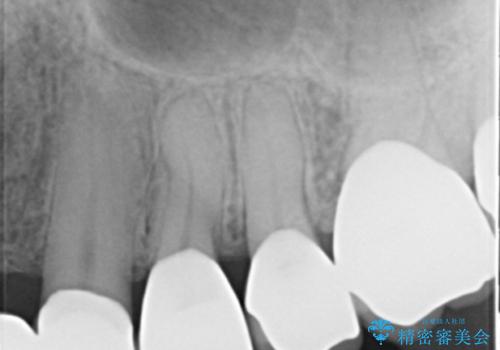

- 左上の一番奥の歯の根の治療を行いつつ、手前の歯の被せ物のやり直しも一緒に行いました。

手前の被せ物は、メタルボンドクラウンだったため、歯ぐきとの境目が黒くなっていたためやり直しを行いました。

オールジルコニアクラウンに変え、審美的な被せ物になりました。

- 約70万円 内訳:ジルコニアクラウン10万円x4、TeC 1万円x4 根管治療15万円、ファイバーコア2万円費用は治療当時の料金となります